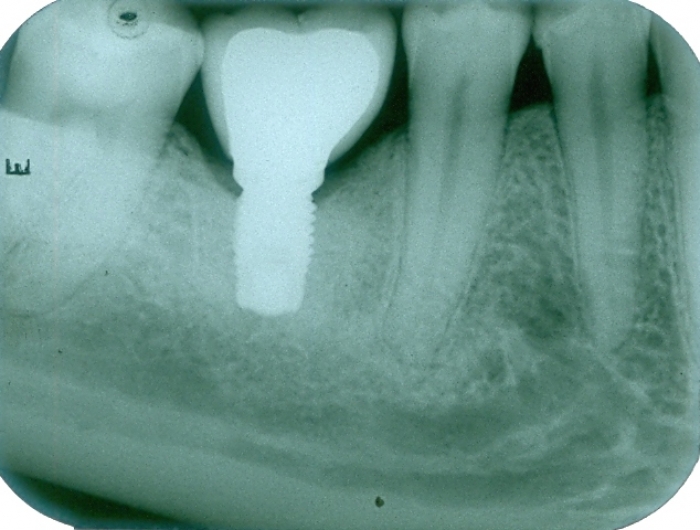

Raio X final após a prótese de porcelana instalada